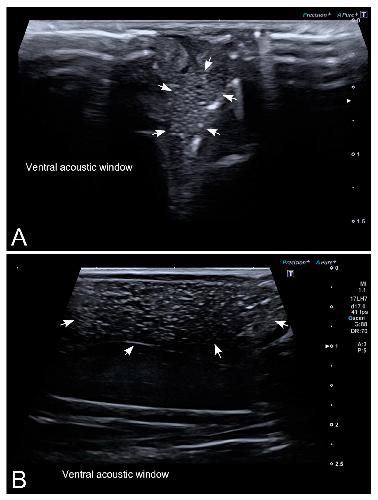

Sex Determination in Two Species of Anuran Amphibians by Magnetic Resonance Imaging and Ultrasound Techniques. , Ruiz-Fernández MJ, Jiménez S, Fernández-Valle E, García-Real MI, Castejón D, Moreno N , Ardiaca M, Montesinos A, Ariza S, González-Soriano J., Animals (Basel). November 18, 2020; 10 (11):